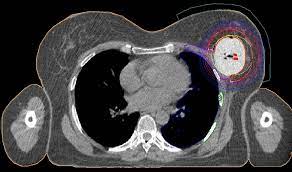

An mri scan of the breast may be. If you have a pet scan: Pet/ct scan combinations detect cancer in its earliest stages, when changes are happening at the cellular level. This combination scan is called a pet/ct. A ct scan of the heart may be ordered when various types of heart disease or abnormalities are suspected. In some cases, physicians use all three imaging techniques. This test may reveal whether breast cancer has spread to the bone. For example, ct has become a useful screening tool for detecting possible tumors or lesions within the abdomen. Learn how this test works, as well as its benefits and risks. It takes pictures from different angles. Why aren't pancreatic ct scans used in routine physical examinations to detect and prevent the spread of pancreatic cancer? A ct scan may be used to look for tumors in organs outside of the breast similar to a ct scan, a pet scan is a way to create pictures of organs and tissues inside the body. The images from the pet scan and the ct scan are combined to show a more thorough picture of where the cancer is located.

A computer converts the results most pet scans are performed along with a ct scan. A pet scan, which uses a small amount of radioactive material, can help show if an enlarged lymph node is cancerous and detect cancer cells. A ct scan of the heart may be ordered when various types of heart disease or abnormalities are suspected. Each has its own strengths. Ct scan of the abdomen. Ct scans can detect bone and joint problems, like complex bone fractures and tumors. During the study, the diagnostician can change the thickness of the cut up to 1 mm. The ct scans, four of them over the course of the 11 weeks from my initial appointment with my primary (23 march). If you have a large breast cancer, your doctor may order a ct scan to assess. Several studies have demonstrated that dog can sniff and detect cancer in the breath or urine sample of a patient. A ct scan is one of the most frequently utilized exams to detect cancer and to show things such as a tumor's shape and size. This test may reveal whether breast cancer has spread to the bone. Preparation for ct of the breast.

Can Pet Ct Replace Separate Diagnostic Ct For Cancer Imaging Optimizing Ct Protocols For Imaging Cancers Of The Chest And Abdomen Journal Of Nuclear Medicine from jnm.snmjournals.org If you have a pet scan: Bone scans, positron emission tomography (pet), and computed tomography (ct) all continue to be employed alone or in combination for the detection of breast cancers suspected to have spread. Doctors use this type of mammogram in women with breast cancer, but with. Computed tomography (ct or cat) scan. Each has its own strengths. The ct can detect some masses that would then need further evaluation. An mri scan of the breast may be. This lung cancer awareness month learn how future processing is able to detect lung cancer from ct scans with the help of ai.